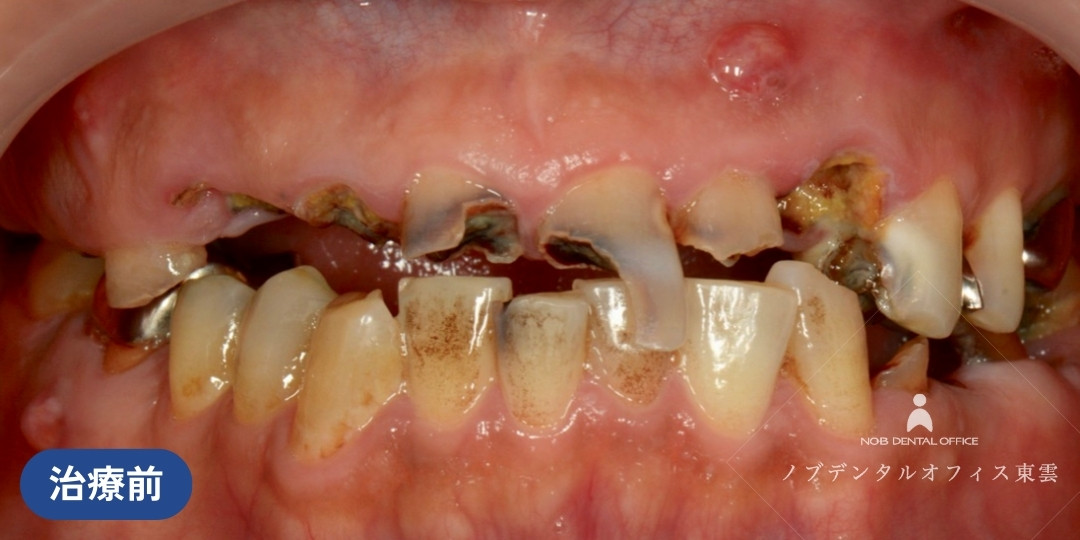

咬合崩壊から機能回復した症例(40代男性の場合)

多数にわたる虫歯・歯周病・かぶせ物の不適合があった方の症例です。

上下の歯が咬み合っておらず、咀嚼機能も低下している状況でした。咬合崩壊(お口全体の噛み合わせのバランスが完全に崩れ、正常に機能しなくなった状態)と診断されました。

虫歯治療など部分的な治療を続けると、残っている他の歯への負担が増え、再治療の繰り返しが予想されます。

初診の時点で「全体的に治療したい」とのことでしたが、まずは応急処置を行い、口腔ドッグによる診察、包括的治療の順に行いました。